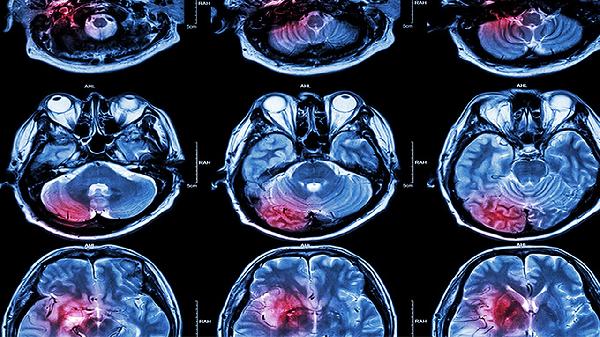

1、材料特性:PEEK材料在生物相容性上表现优异,植入后不易引起排异反应,同时其轻量化的特点减轻了头部的负担,透光性也便于术后影像学检查。钛网则以其高强度和耐用性著称,能够提供良好的支撑效果,但在CT或MRI检查中可能出现伪影,影响影像结果的准确性。